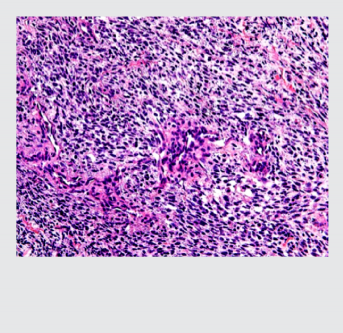

midiendo entre 1 a 4 cm, de gris blanquecino, aspecto fibroso y áreas friables. Los hallazgos mi- croscópicos mostraron una neoplasia dispuesta en sábanas con células ahusadas de citoplasmas eosinófilos pálidos, con plasmalemas (membranas plasmáticas) no bien definidas, núcleos centrales, grandes, pleomórficos e hipercromáticos, con presencia de alta actividad mitótica; (foto 2). El tumor se acompañaba de extensas zonas de necrosis y los bordes quirúrgicos estuvieron comprometidos. El reporte de inmunohistoquímica indicó CD56 positivo (++ / +++) en células proli- ferantes; vimentina positivo; BCL2 positivo (+++) en células proliferantes; cromogranina negativo; S100 negativo; CD34 positivo en pocas células proliferantes (control interno positivo en vasos); Ki-67 positivo (70%); (foto 3). El diagnóstico fue referido como neurofibroma con atipia e índice de proliferación nuclear alto (70%).

Foto 2. Imagen microscópica de la tumoración. Tinción con hematoxilina-eosina que muestra células en huso de citoplasma eosinófilo.